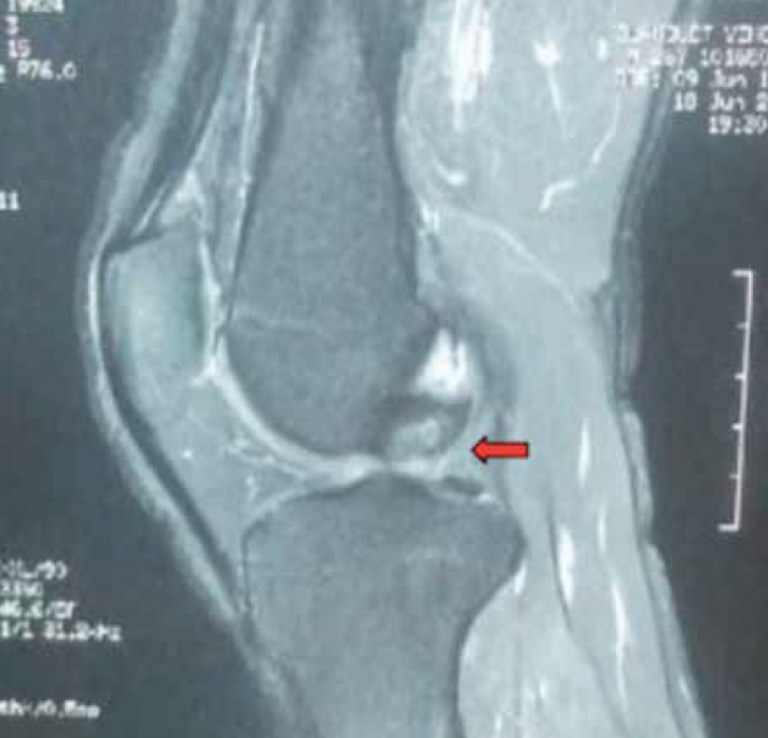

IRM en coupe sagittale objectivant la rupture du LCP (flèche).